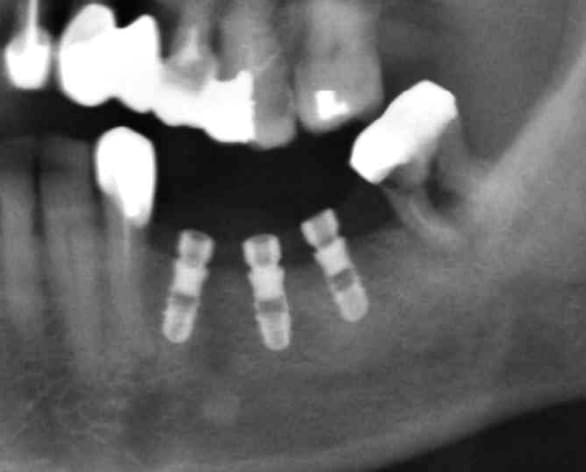

le cas de ce matin

Patient 80ans ne veut plus de PAP

et son fils a un implant en bouche, alors!!!!!!!!!!!!!!

Première tentative en transgingival